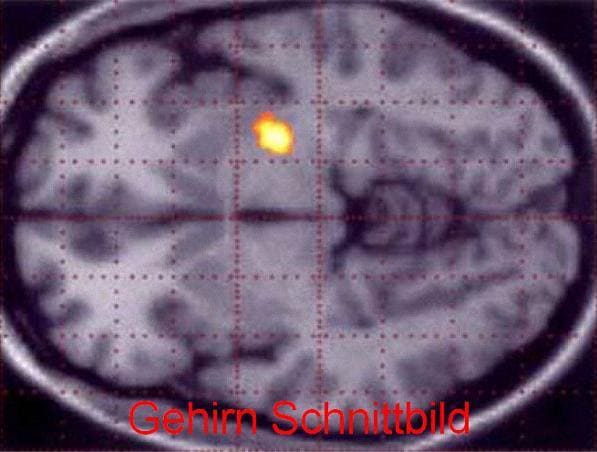

Es gibt eine Reihe weiterer, meist seltener Erkrankungen wie Multisystematrophie, Kortikobasale Degeneration, Progressive Supranukleäre Paralyse, Essentieller Tremor und die Wilsonsche Erkrankung (Hepatolentikuläre Degeneration) die ähnliche Beschwerden wie die Parkinsonsche Krankheit hervorrufen. Diese sind in der neurologischen Abklärung mit bildgebenden Verfahren (z.B. Magnetresonanztomographie des Gehirns), neuropsychologischen Untersuchungen und Labortests zu differenzieren.